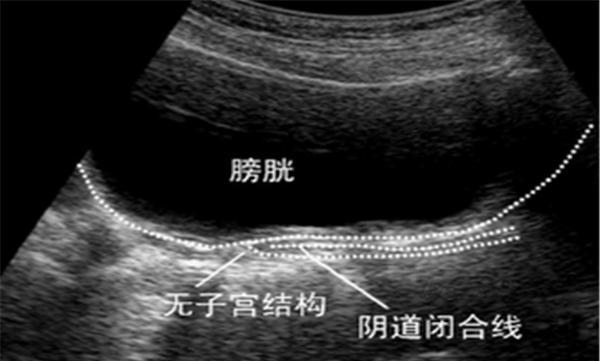

假石女:先天有子宫,但阴道处女膜闭锁或阴道横隔,每次来月经会痛经

性的阴道缺失或者阴道闭锁的女性假石女是指阴道及其它深知其发育良好

二,什么是真石女,什么是假石女

子宫的发育不良或缺失;假石女则属于处女膜闭锁(或肥大)或者阴道横膈

假石女的特点:有些女性的内生殖器官是完好的,各个内生殖器例如子宫